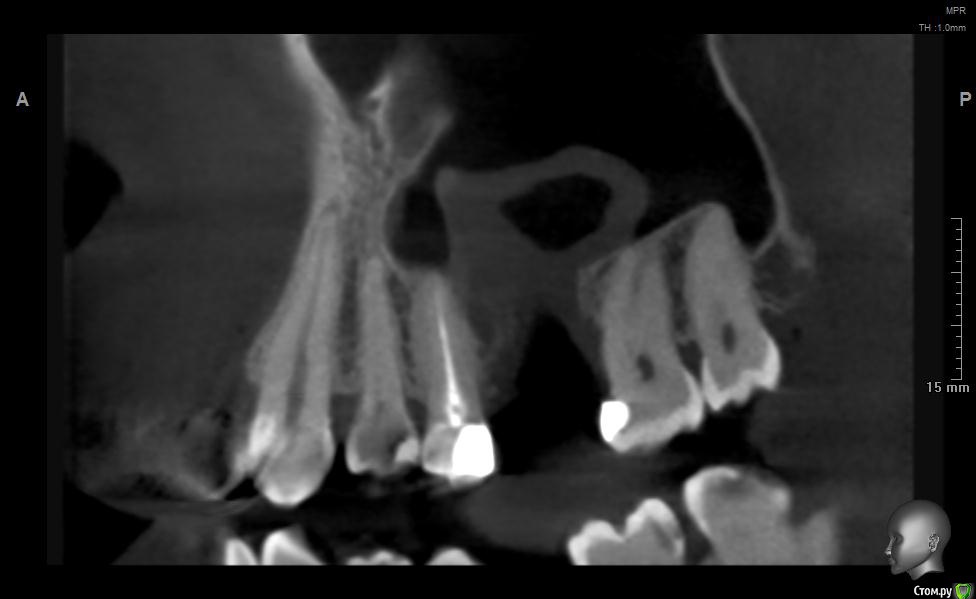

jm3300 Опубликовано 20 мая, 2019 Поделиться Опубликовано 20 мая, 2019 Добрый день. Пациент не мой, причины удаления, а так же о ходе удаления сказать ничего не могу. Известно лишь, что после удаления из лунки получили много зеленоватой жидкости. Удаляли с месяц назад. До сих пор имеется не сильно зияющая дырка. Нужно что то делать или просто ждать пока вторичным затянется. И если имплант планировать- ожидать ли там самостоятельного появления обьема кости? Ссылка на комментарий

L.E.S.I.K. Опубликовано 20 мая, 2019 Поделиться Опубликовано 20 мая, 2019 Я бы сделал ревизию через лунку, убрал оболочку кисты (похоже что она там осталась, или это эпителий врос - не важно) и провел бы закрытие небным лоскутом. При направлении в ЧЛХ есть вероятность, что наведут "разруху"(по Колддвел-Люк) и пациент получит проблему при дальнейшей реабилитации. З.Ы. На данных срезах не видно остиомеатальный комплекс- крайне желательно, чтобы он был не блокирован. 3 Ссылка на комментарий

Дмитрий М Опубликовано 21 мая, 2019 Поделиться Опубликовано 21 мая, 2019 месяц прошел, уже ничего не дождетесь, кость там не вырастет т.к. уже пошла эпителизация. так и останется не сильно зияющая дырка только вы видите клиническую картину, поэтому вам решать какой вариант лучше выбрать.в любом случае удалять кисту, оболочку, вероятно будет сообщение, которое необходимо закрывать и по ситуации готовиться к обоим вариантам по снимкам это скорее киста, (прослеживается кортикальная по контуру) 1 Ссылка на комментарий

Дмитрий Л. Опубликовано 21 мая, 2019 Поделиться Опубликовано 21 мая, 2019 Там уже есть сообщение с гайморовой. Возможно не функционирующее. Вяло текущий хронический воспалительный процесс. Ждать мало смысла. Если стремиться сделать всё как можно менее инвазивно, можно пойти по такому пути:1. Недельку попромывать соустье антисептиками. Воспаление стихнет. Десны добавится.2. Расскрыться. Аспирировать слизистую слюноотсосом. Кюретаж, всё через лунку. Если функционирующего соустья не было, оно появится.3. Небный лоскут, чтоб ушить соусье. Сосудосуживающие в нос, антибиотики. Ссылка на комментарий

jm3300 Опубликовано 21 мая, 2019 Автор Поделиться Опубликовано 21 мая, 2019 Ну по КТ и клинически сообщения с пазухой нет. Пациента,кроме наличия самой лунки, вообще ничего не беспокоит. Ссылка на комментарий